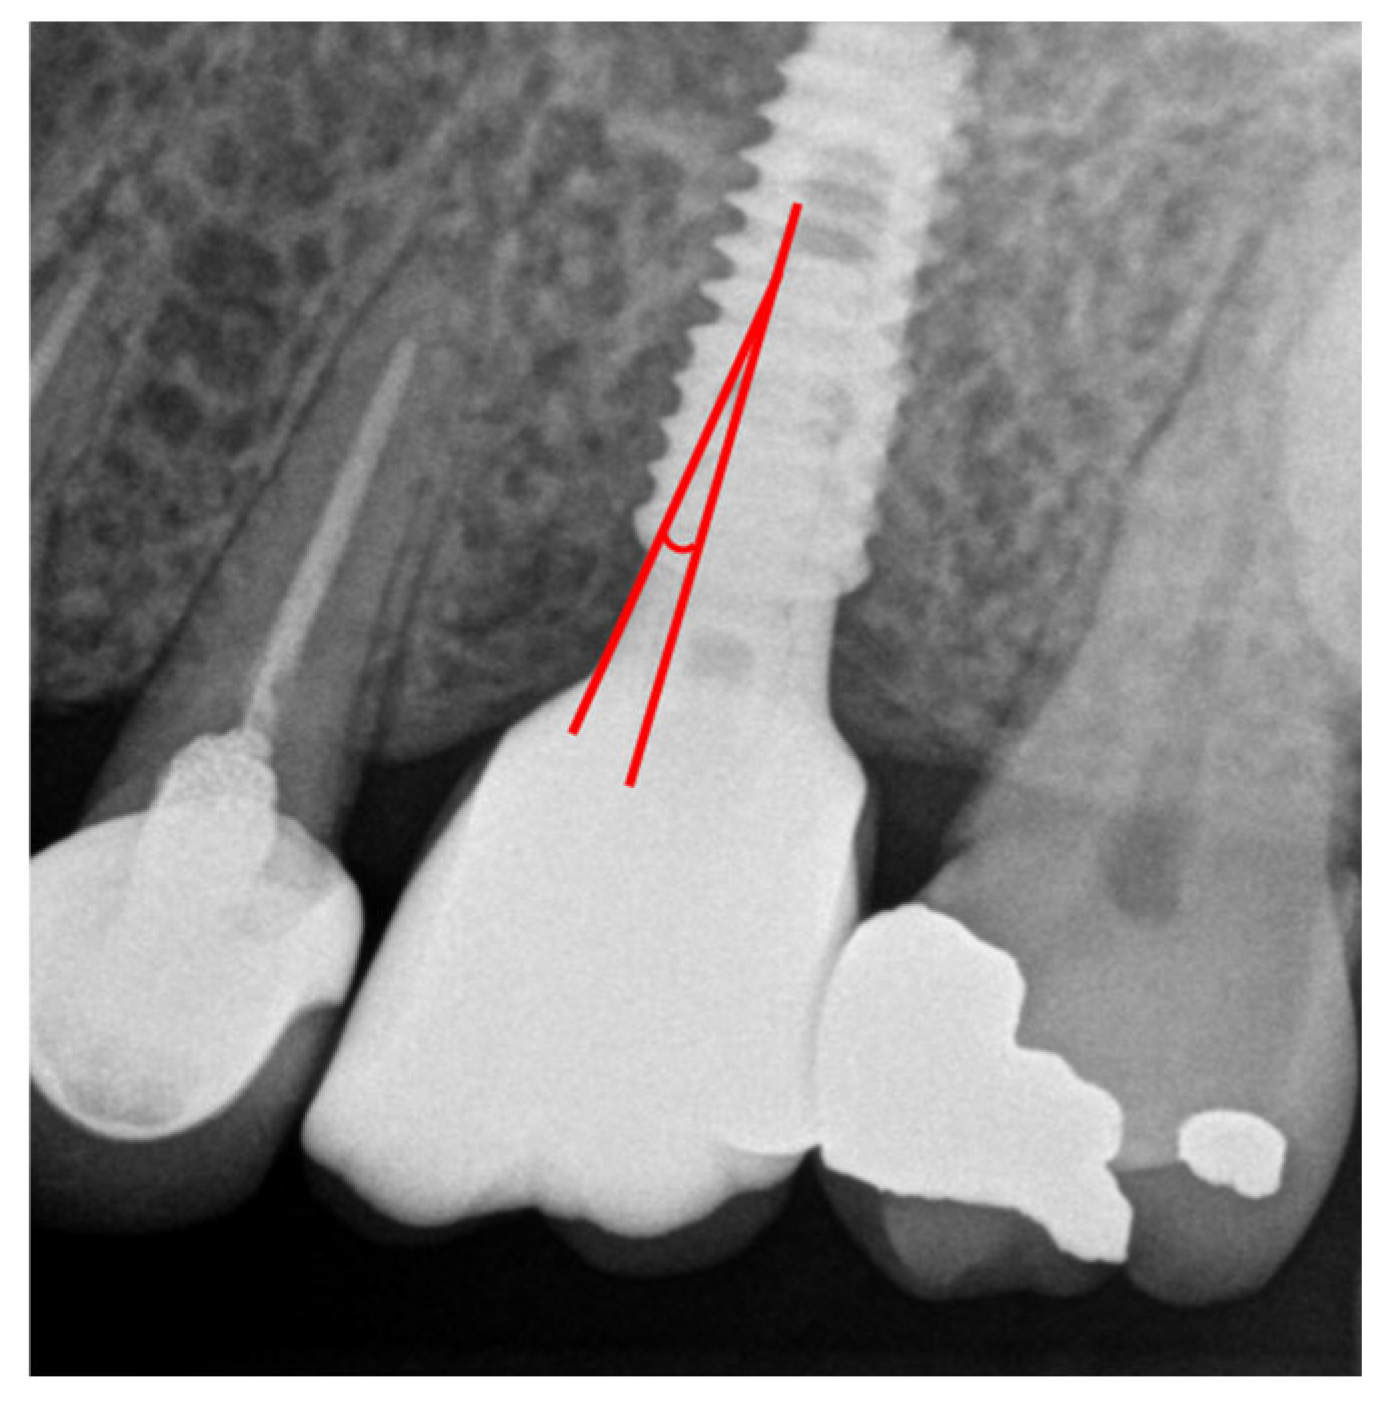

All measurements were independently performed by two calibrated periodontal trainees. If inter-examiner differences exceeded 0.5 mm, remeasurement was performed and a consensus value was obtained. Representative radiographic examples and measurement procedures are illustrated in Figure 1.

Abutment angulation was defined as the angle formed between the long axis of the implant fixture and the axis of the abutment. Based on previous biomechanical and clinical studies reporting increased non-axial loading beyond this threshold, abutment angulation was dichotomized as <30° or ≥30°. This cutoff was selected to reflect biomechanical and clinical evidence demonstrating a marked increase in non-axial loading and crestal bone stress when abutment angulation exceeds approximately 30 degrees.

Figure 1. Representative standardized periapical radiograph illustrating the measurement of abutment angulation, defined as the angle between the long axis of the implant fixture and the axis of the abutment, and the assessment of peri-implant marginal bone level (MBL), defined as the vertical distance from the implant platform to the most coronal bone-to-implant contact on the mesial and distal aspects, as used for quantitative analysis in the present study.